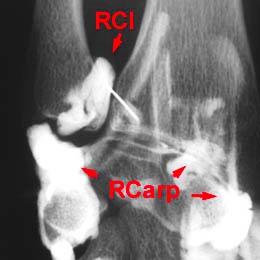

A - Arthrographie de la radio-ulnaire distale - vue initiale : Cliché avant injection. A noter, une opacification préalable de la radio-carpienne permettant de bien silhouetter le bord inférieur du ligament triangulaire.

B - Arthrographie de la radio-ulnaire distale - vue tardive : Remplissage de l'articulation par du contraste. Pas d'extravasation, pas de fissuration de la partie proximale du ligament triangulaire. Pas d'opacification de la gaine de l'extenseur ulnaire du carpe.

Arthrographie normale de la radio-ulnaire distale